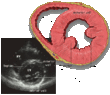

| Each figure contains a TTE with a black background, and a corresponding colored illustration. | Patrick J. Lynch and C. Carl Jaffe, Yale University, 2006. | ||||||||||

| Click on a figure to enlarge it and see some parts of the heart identified. RV, right ventricle; LV, left ventricle; RA, right atrium; LA, left atrium; TV, tricuspid valve; MV, mitral valve; AV, aortic valve; RVOT, right ventricular outflow tract; LVOT, left ventricular outflow tract | |||||||||||